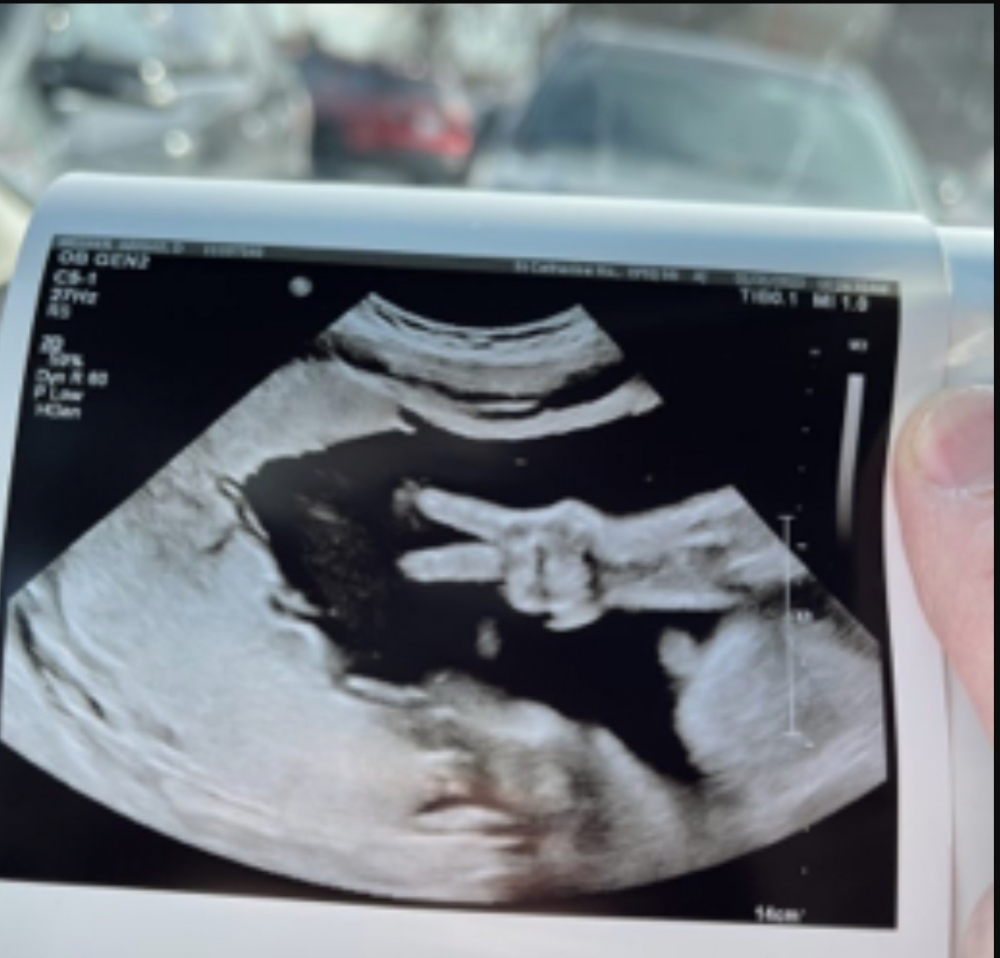

根據外國傳媒報導,來自美國印第安納州的準媽媽Abigail Weener,和老公Kyle Weener育有2名孩子,如今又即將迎接第3個孩子。發圖時Abigail懷孕已達31周,也知道是女兒故改名Ellie,他們如常到醫院進行進行產檢和做超聲波檢查,這時候竟拍攝到Ellie擺出「Yeah」的手勢,而且非常清晰,令Kyle忍不住把照片放上網分享,並表示:「Ellie過上最好的生活!平安!」(Ellie’s living her best life!Peace out!)

網民們一方面讚照片很奇妙,也有人質疑照片的真實性。Kyle之後有貼出新照片,為Ellie比「Yeah」之前拍攝到,並在照片指出寶寶的臉、頭髮、手指、手臂。Kyle補充醫護人員是拍到這張照片想要趕快擷取,才機緣巧合拍到寶寶比「Yeah」的畫面。拍到照片的一刻,醫護人員立即望著夫婦二人,隨即哄堂大笑,Kyle回憶說:「工作人員說他們以前從未見過這樣的事情」。對Kyle這位準爸爸說,也正好提醒他上帝正在妻子的肚內建造小生命。